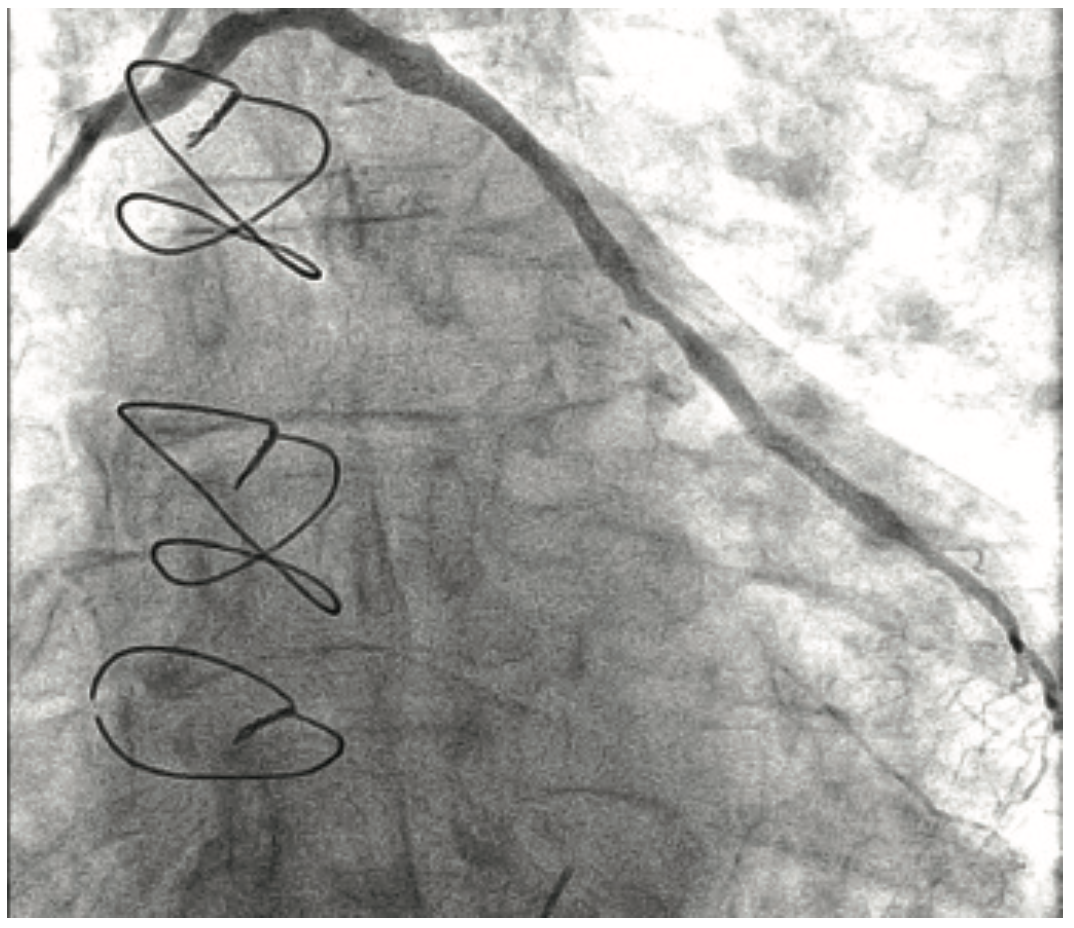

The patient’s prior procedures were performed via transfemoral approach and on one occasion, she experienced severe local pain due to vascular hemorrhage. The coronary brachytherapy procedure was performed using left radial artery access with a 6 Fr 10 cm long Slender Glidesheath (Terumo) and anticoagulation with bivalirudin. Baseline angiography showed sequential, high-grade restenotic lesions in the proximal right coronary artery (RCA) stents in addition to significant stenosis at the outflow of the most distal stent (Figure 2A). The in-stent restenosis was treated with laser atherectomy using an X-80 excimer catheter (Spectranetics) followed by balloon angioplasty with a 3.5 mm Angiosculpt scoring balloon (Spectranetics) and 4.0 mm NC Euphoria balloon (Medtronic). The most distal lesion, which extended beyond the prior stents, was treated with a new Promus DES. Coronary brachytherapy of the proximal lesions was then performed with a Beta-Cath 40 mm long source for a treatment dose of 23 Gray (Figure 2B). Final angiographic result is shown in Figure 2C. Repeat cardiac catherization at 3 months, performed because of chest pain, demonstrated widely patent stents. The patient has continued on aspirin and clopidogrel, and remains symptom-free 1 year post procedure.